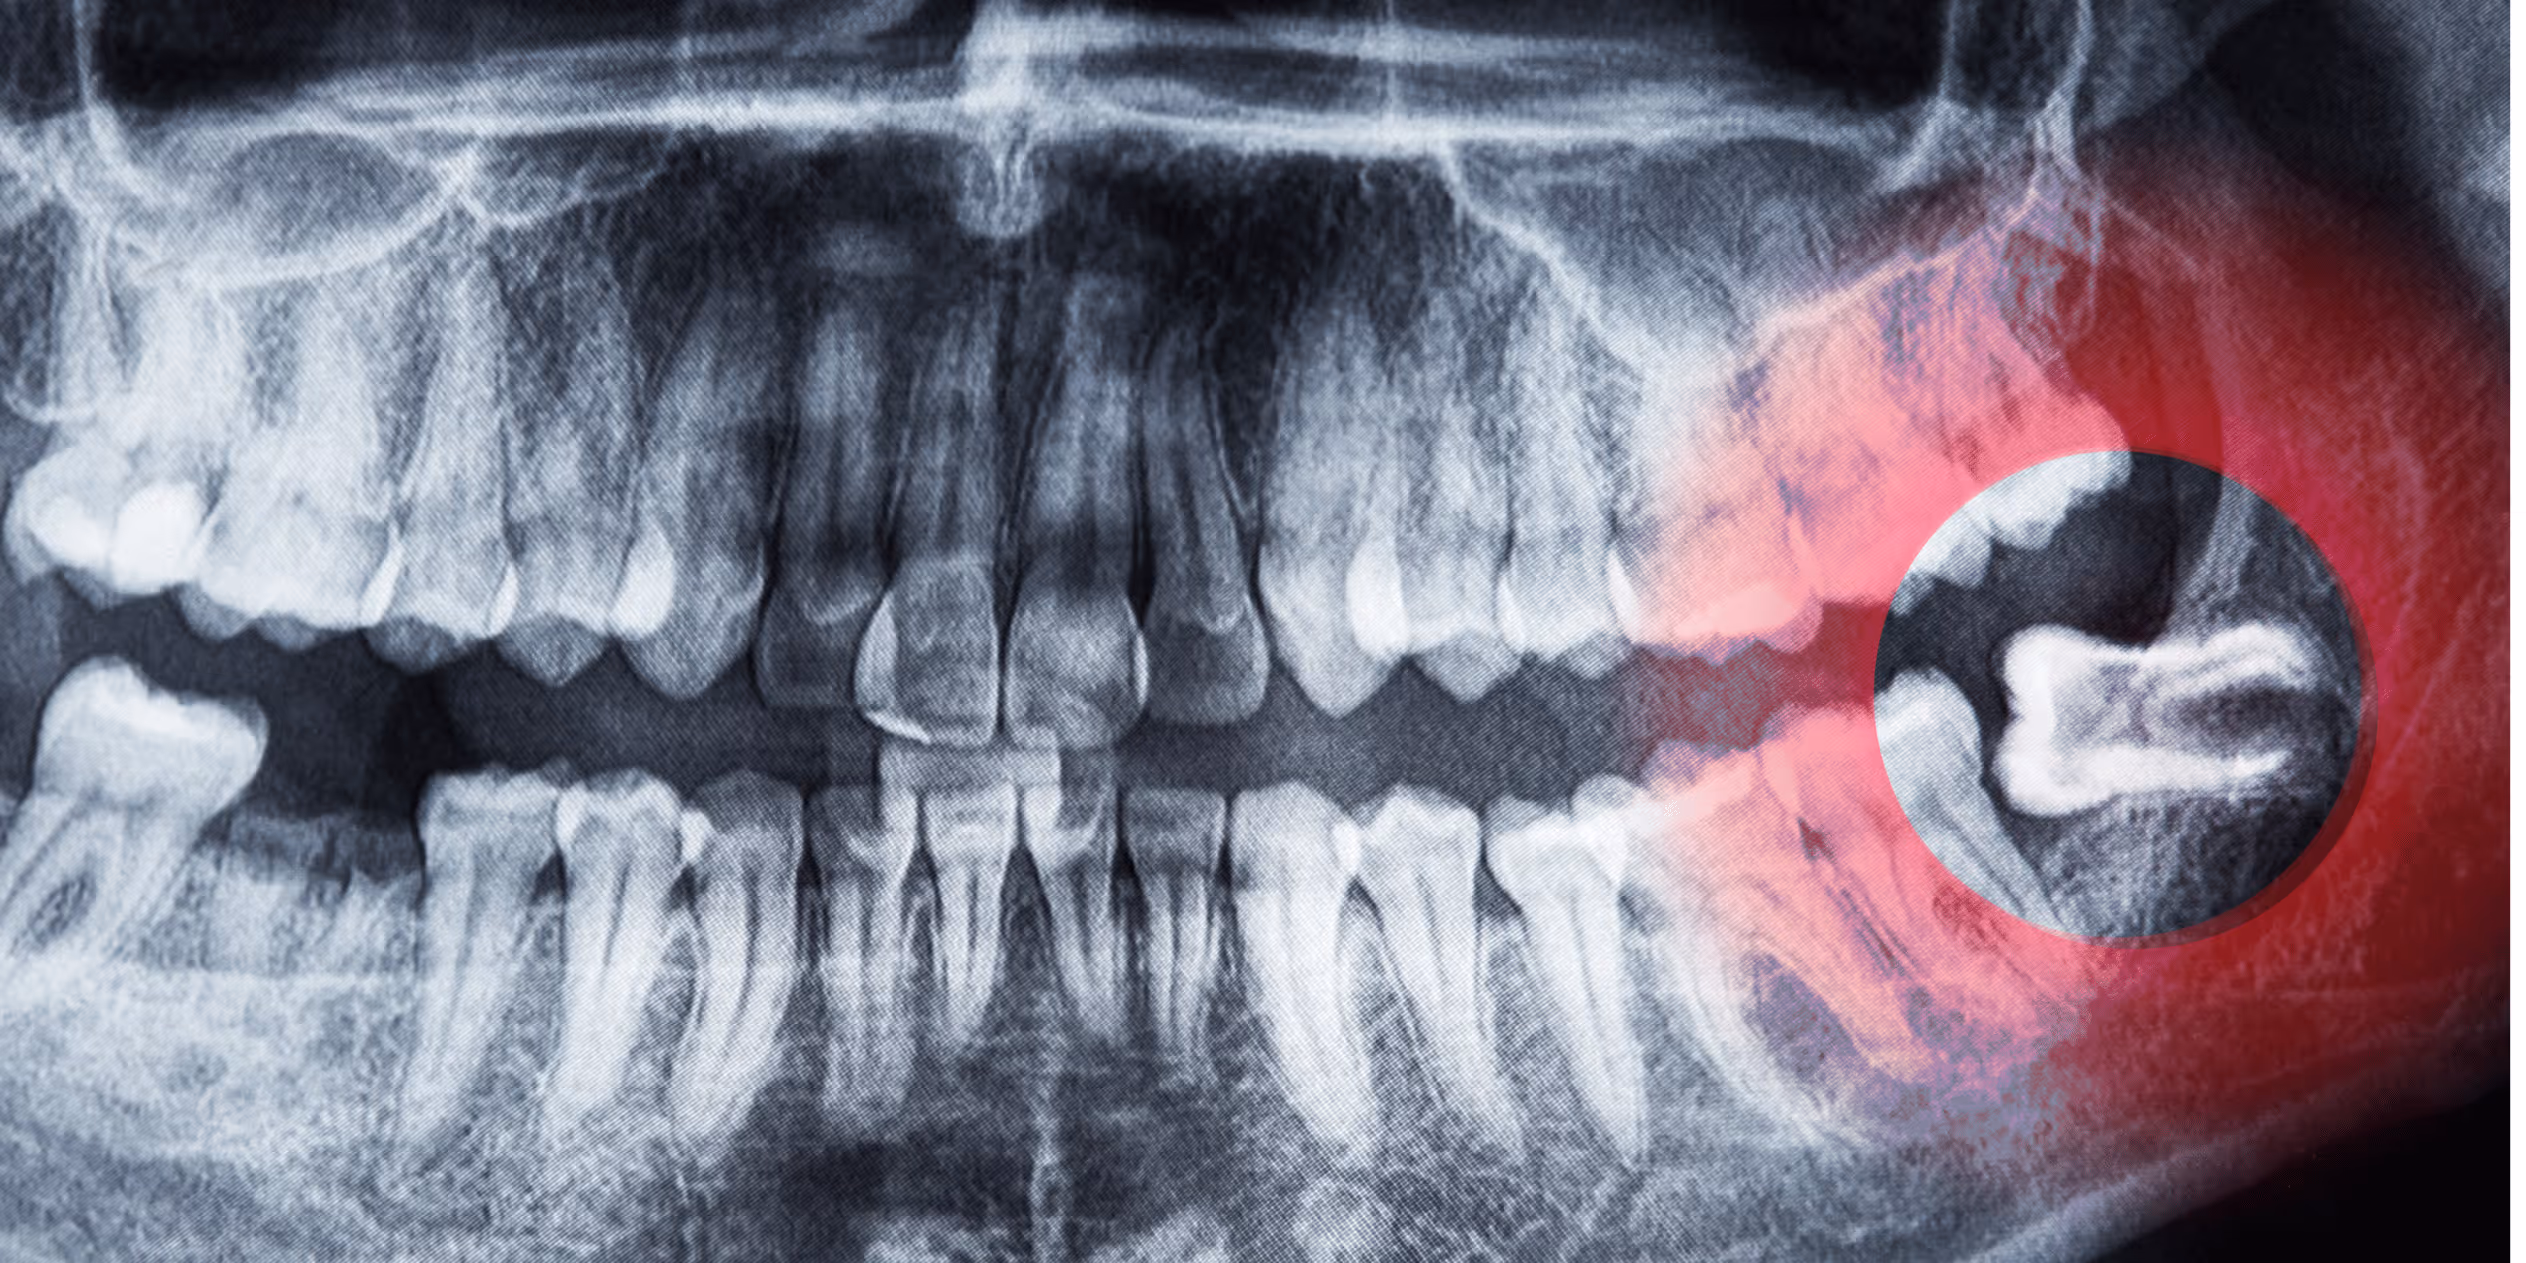

In vielen Fällen bleiben Weisheitszähne deshalb ganz oder teilweise im Kieferknochen verborgen – sogenannte retinierte Weisheitszähne. Andere wiederum brechen schief durch oder drücken auf die benachbarten Backenzähne. Solche Konstellationen können zu chronischen Entzündungen, Karies an angrenzenden Zähnen, Zystenbildung oder sogar Zahnverschiebungen führen.

Die Entscheidung zur Entfernung wird immer individuell und nach genauer Untersuchung getroffen. In der Ordination in Hollabrunn kommen dafür modernste bildgebende Verfahren wie digitale Volumentomographie (DVT) zum Einsatz, um die genaue Lage und Ausrichtung der Zähne sowie die Nähe zu empfindlichen Strukturen wie Nerven zu beurteilen.